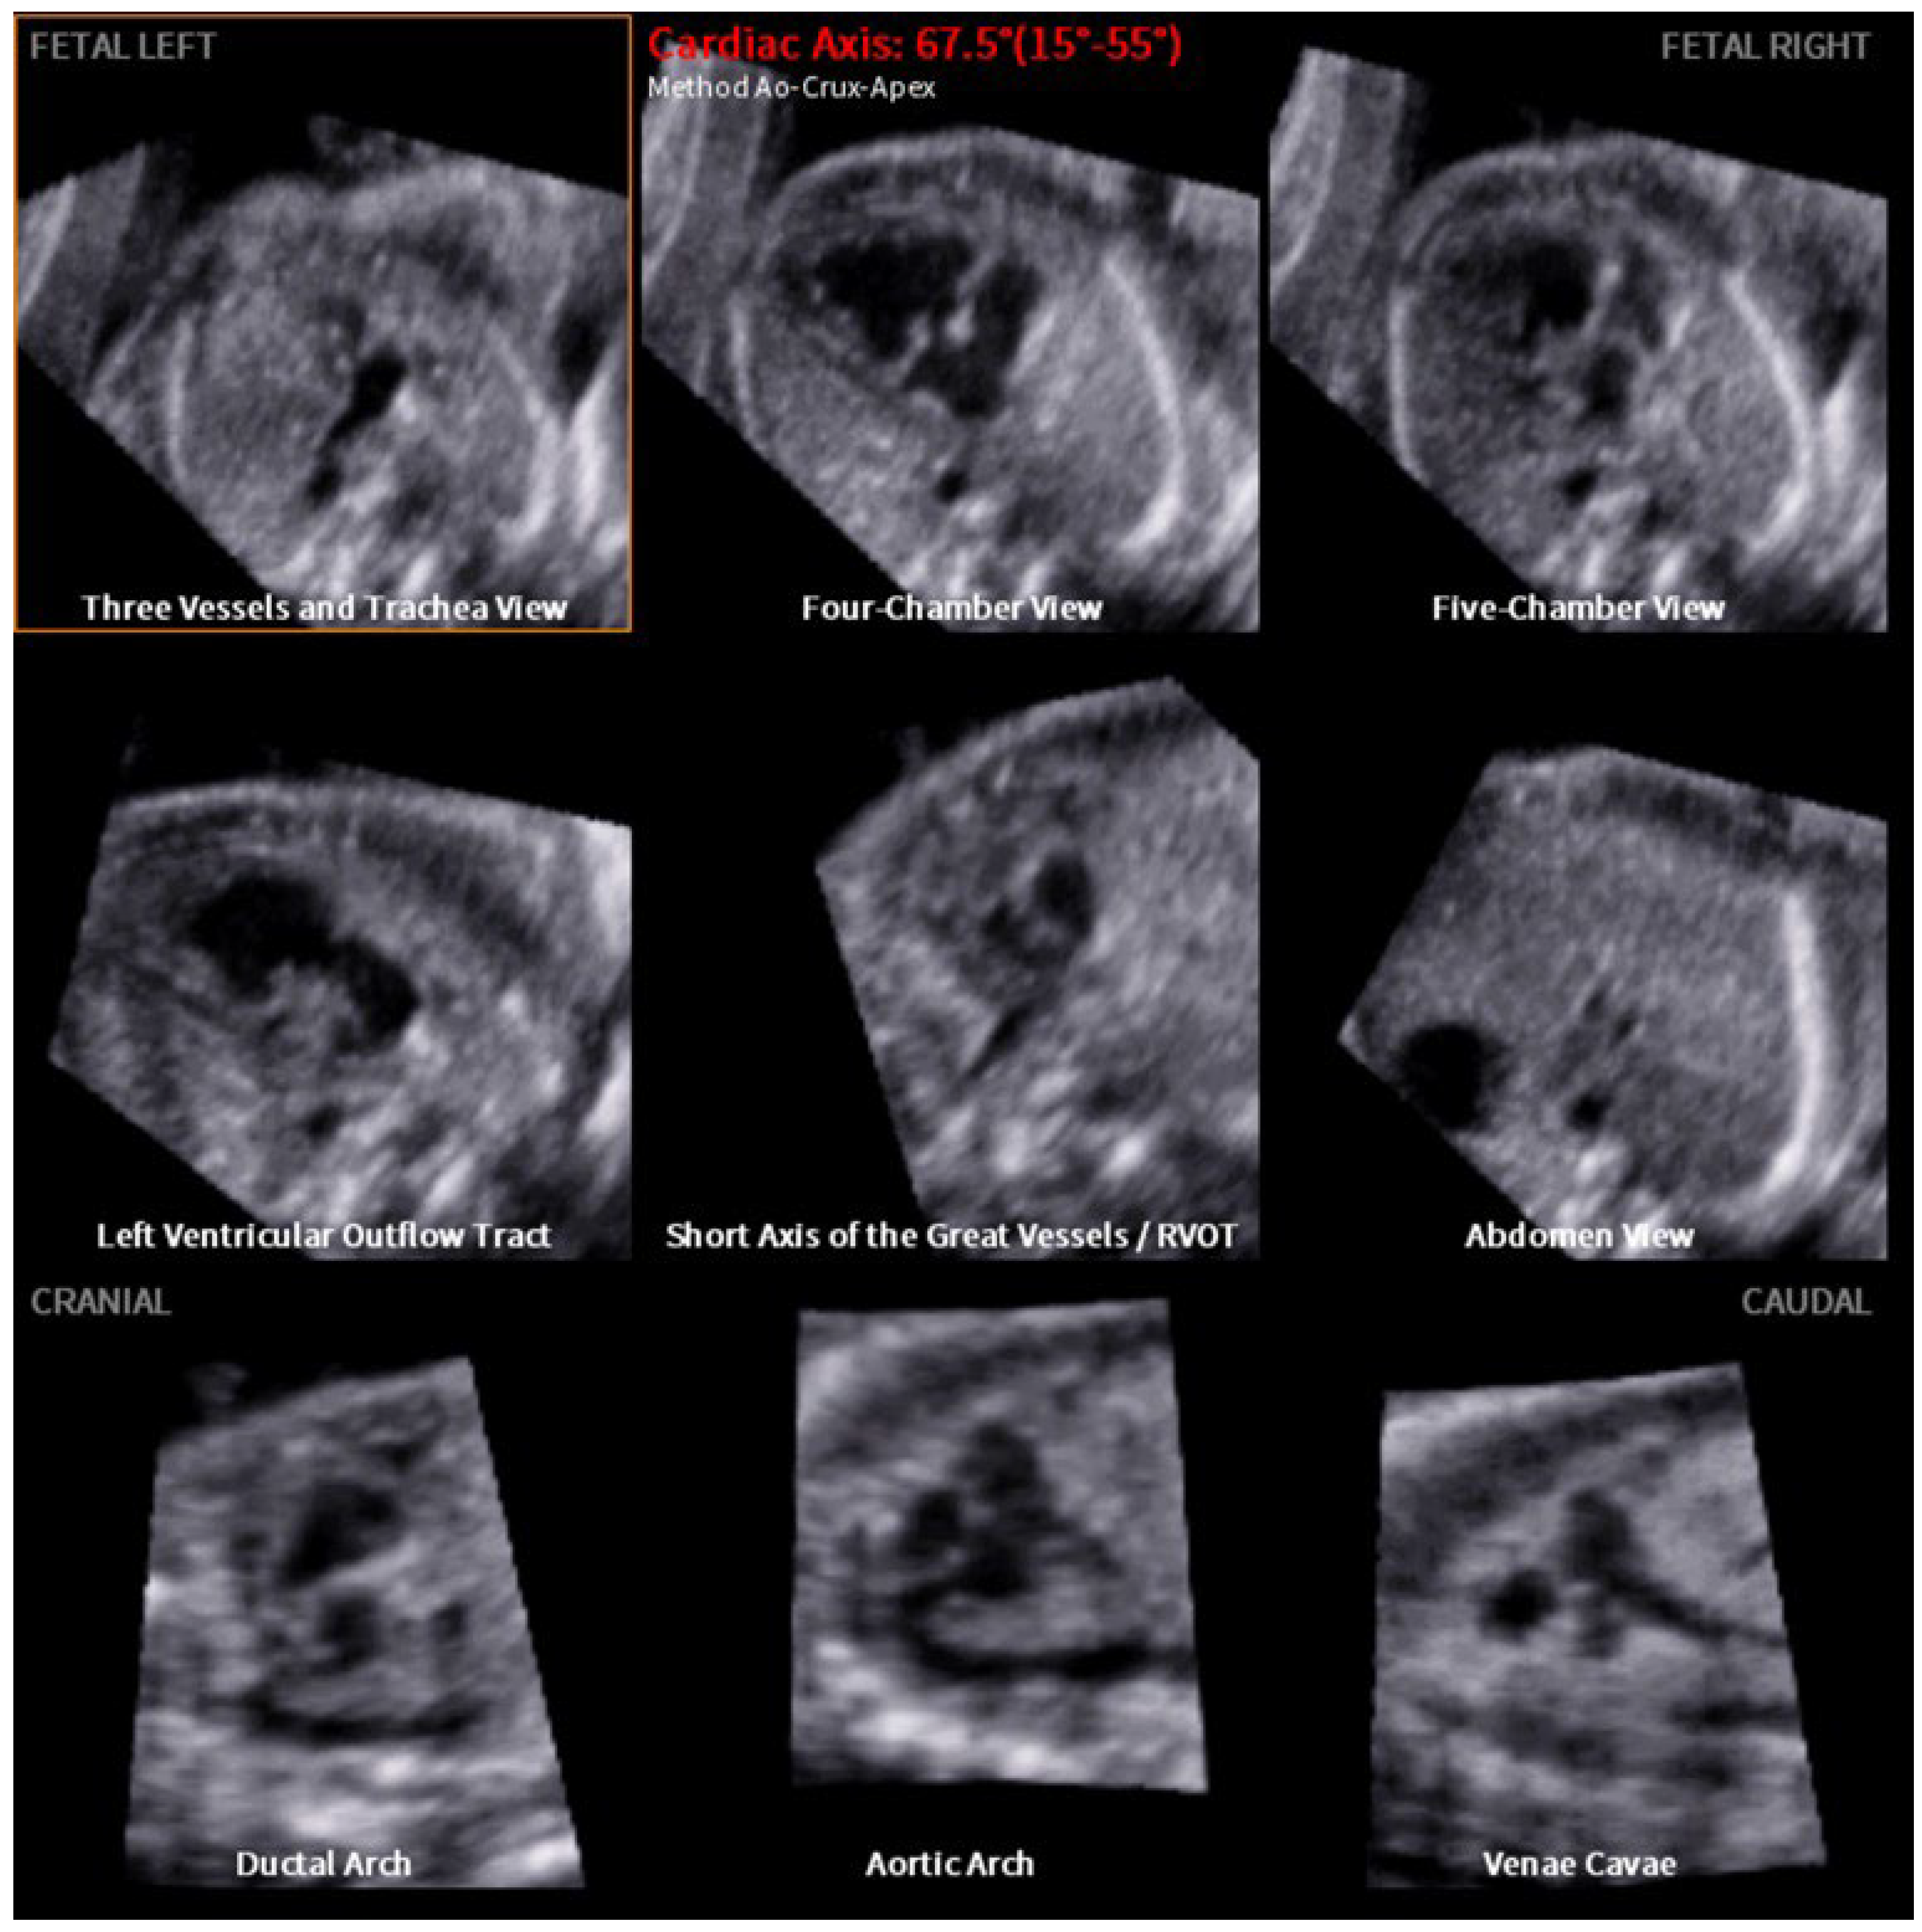

- Yeo, L.; Romero, R. Fetal Intelligent Navigation Echocardiography (FINE): A novel method for rapid, simple, and automatic examination of the fetal heart. Ultrasound Obstet. Gynecol. 2013, 42, 268–284. [Google Scholar] [CrossRef] [PubMed]

- Yeo, L.; Romero, R. Color and power Doppler combined with Fetal Intelligent Navigation Echocardiography (FINE) to evaluate the fetal heart. Ultrasound Obstet. Gynecol. 2017, 50, 476–491. [Google Scholar] [CrossRef]

- Yeo, L.; Romero, R. New and advanced features of fetal intelligent navigation echocardiography (FINE) or 5D heart. J Matern Fetal Neonatal Med. 2022, 35, 1498–1516. [Google Scholar] [CrossRef] [PubMed]